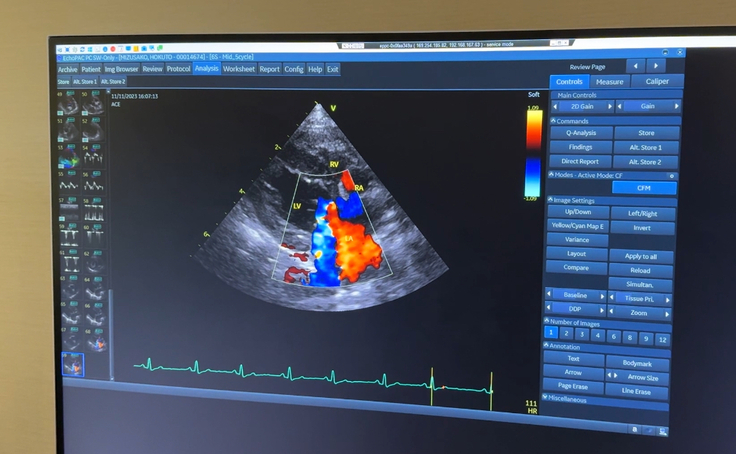

▽エコー写真

エコーはかかりつけの病院で見ていた状態と同じで、血液の逆流はやはり多いです。